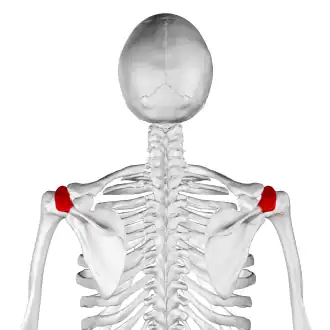

![]() Skeleton, posterior view. Acromion of each scapula shown in red. | |

In human anatomy, the acromion (from Greek: akros, "highest", ōmos, "shoulder", pl.: acromia) or summit of the shoulder is a bony process on the scapula (shoulder blade). Together with the coracoid process, it extends laterally over the shoulder joint. The acromion is a continuation of the scapular spine, and hooks over anteriorly. It articulates with the clavicle (collar bone) to form the acromioclavicular joint.[1]